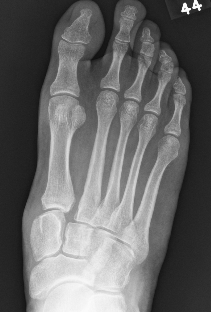

1. Diastasis of the intermetatarsal gap between the 1st and 2nd metatarsals

2. Widening of the space between the medial cuneiform and base of 2nd metatarsal

3. Second metatarsal Fleck sign - avulsion of Lisfranc ligament from base of 2nd metatarsal

4. Widening of inter-cuneiform distance

6. Tarsometatarsal alignment disruption

- medial border 1st metatarsal aligns with medial border medial cuneirform (AP foot)

- medial border 2nd metatarsal aligns with medial border middle cuneiform (AP foot)

- medial border 3rd metatarsal aligns with medial border lateral cuneiform (AP view)

- medial border 4th metatarsal aligns with medial border of the cuboid (oblique view)